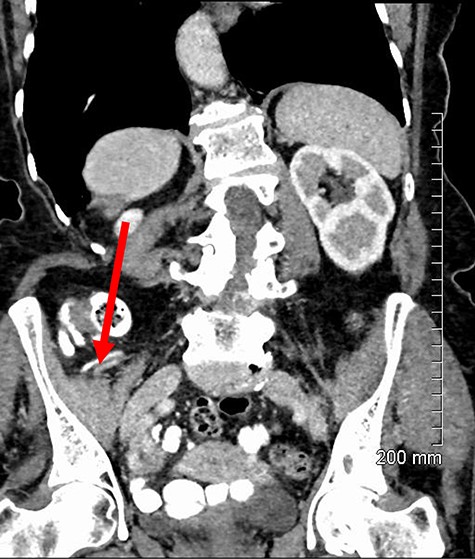

Repair was performed via a transinguinal (Lotheissen’s) approach. An incision was made just superior to the inguinal ligament and a femoral hernia was identified. The sac was dissected free and opened, revealing a gangrenous appendix (Fig. 2). There had been no preoperative suspicion for appendiceal involvement or strangulated contents, with normal lab studies and the appendix located remotely from the hernia on previous imaging (Fig. 3). The diagnosis of DGH was made intraoperatively. Abdominal access was achieved through the initial incision to facilitate an open appendicectomy. The mesoappendix and base of the appendix were ligated with sutures and delivered for further histology. The hernia sac was then transfixed and excised. A primary repair was performed with a non-absorbable suture.

Sagittal contrast-enhanced CT showing a retrocecal appendix (red arrow) discreet from the observed hernia.